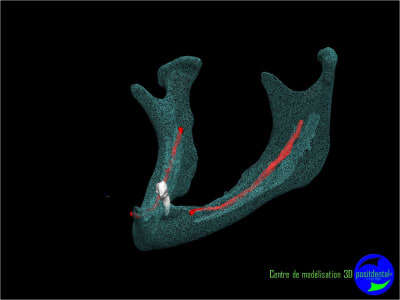

Résorbée genre comme ça?

Sur une mandibule fortement résorbée la pose de 2 implants ne vont pas résoudre les douleurs occasionnées par la compression du nerf dentaire inférieur.